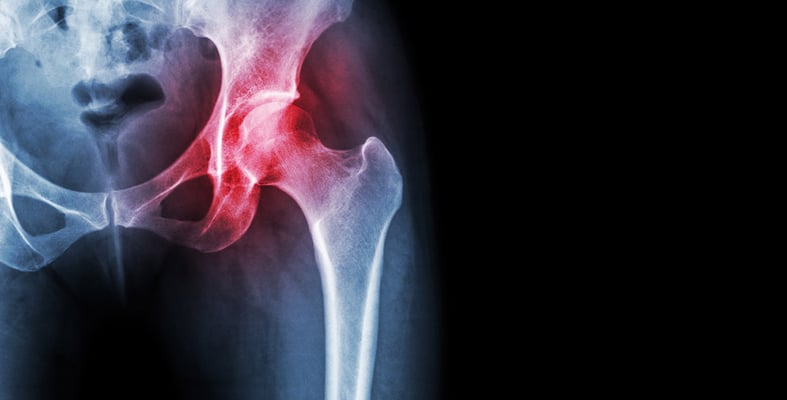

ما هي الغضاريف وما أنواعها ووظائفها؟